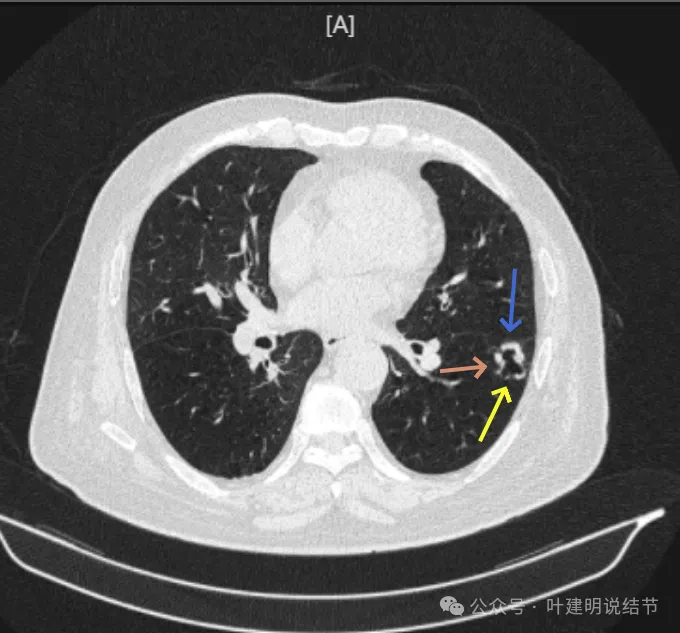

先看2024年6月的影像:

靠叶裂侧密度高、实性,灶内空腔多房,有微小血管走向并进入病灶的囊壁内,叶间裂有受牵拉。

囊壁明显厚薄不均,内壁也不光滑,而整体轮廓与边界却较为清楚。

部分边缘有细毛刺样征、中间密度低些,边上有囊腔,有的地方有少许磨玻璃成分,见到有小血管多处进入病灶。